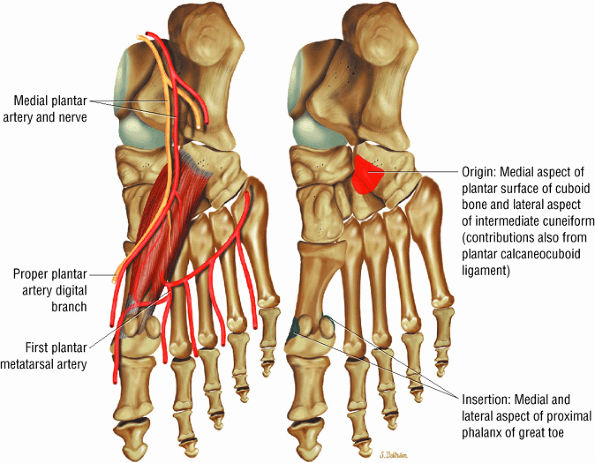

The muscles of the foot are the extensor digitorum brevis (Fig. 5.14), the abductor hallucis (Fig. 5.15), the flexor digitorum brevis (Fig. 5.16), the abductor digiti minimi (Fig. 5.17), the quadratus plantae (Fig. 5.18), the lumbricals (Fig. 5.19), the flexor hallucis brevis (Fig. 5.20), the adductor hallucis (Fig. 5.21), the flexor digiti minimi brevis (Fig. 5.22), the dorsal interossei (Fig. 5.23), and the plantar interossei muscles (Fig. 5.24).

FIGURE 5.20 ● FLEXOR HALLUCIS BREVIS The flexor hallucis brevis functions in flexion of the great toe. Instability of the first metatarsophalangeal joint occurs with loss of flexor hallucis brevis function, as occurs with excision of both tibial and fibula sesamoids.